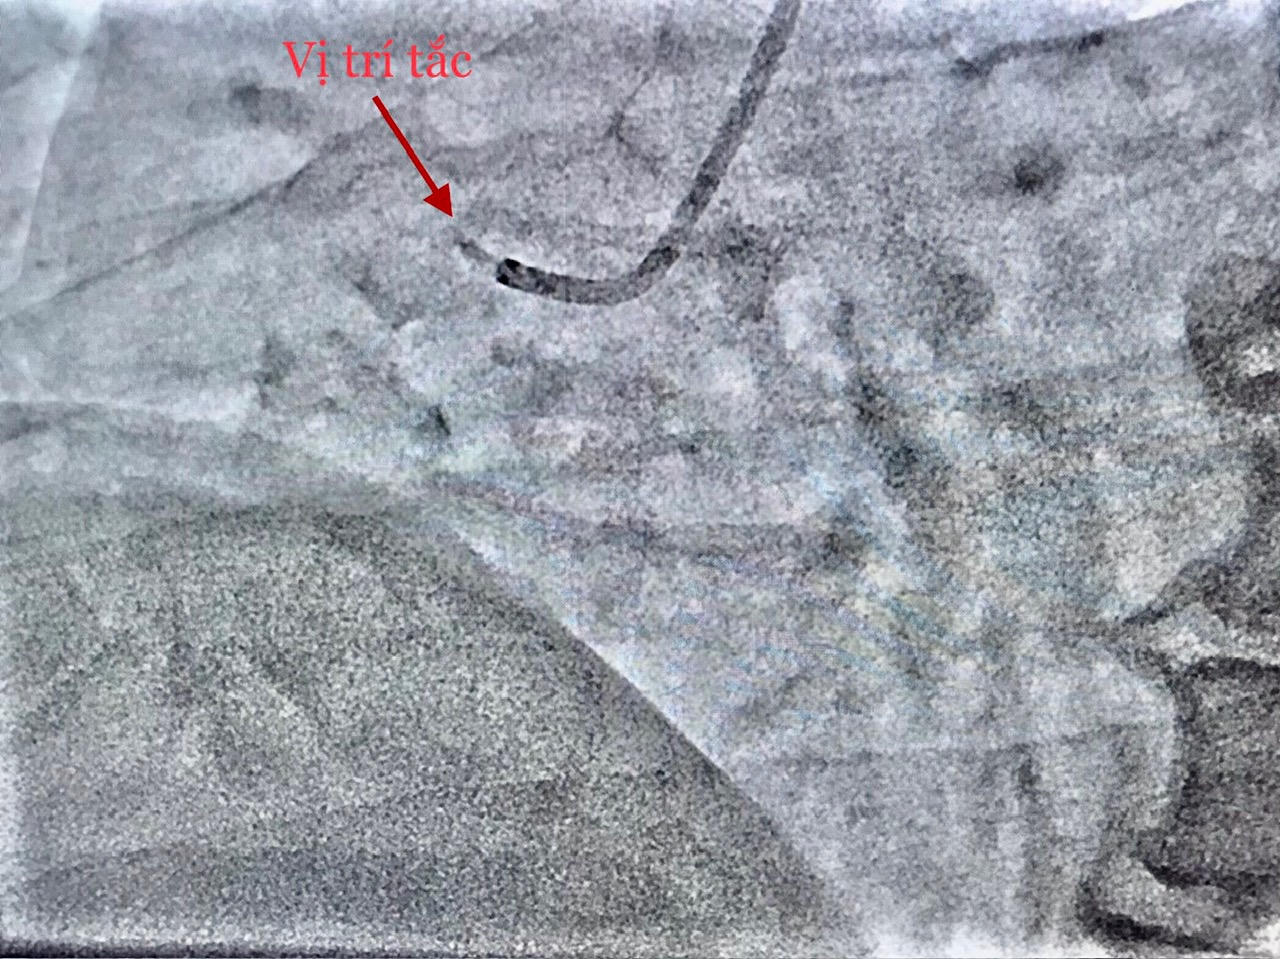

Hình DSA mạch não trước can thiệp |

Ê-kíp can thiệp tim mạch trong thời gian khoảng 40 phút đã hoàn tất nong động mạch vành bị tắc và tiến hành đặt giá đỡ (stent), giúp tái lập dòng máu nuôi tim. Ngay sau đó ê-kíp can thiệp mạch não chụp kiểm tra phát hiện tắc động mạch não giữa bên phải; thủ thuật lấy huyết khối tái thông mạch máu bị tắc với thời gian 20 phút.

Thời điểm chuẩn bị đặt ống thông để can thiệp mạch vành, bệnh nhân liệt nửa người bên trái và nói đớ. Nhận định đây là một trường hợp hiếm gặp phối hợp giữa nhồi máu cơ tim cấp (do tắc động mạch vành) và nhồi máu não cấp (do tắc một mạch máu ở não), ê-kíp can thiệp mạch máu não lập tức được báo động để cùng phối hợp điều trị cho bệnh nhân. Kết quả CTscan não đúng như chẩn đoán.